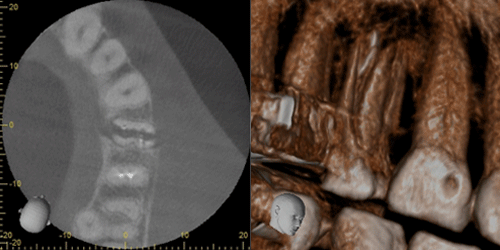

コンピュータを駆使したデータ処理と画像の再構成で、断層写真を得ることができる装置です。歯科用CTとは、近年開発された歯科に特化したCT装置で、コーンビーム方式を用いているためコーンビームCTとも言われています。従来のX線写真は二次元的な平面での診断しかできませんが、歯科用CTでは三次元の立体画像でのレベルに変わるので、より多くの情報が得られます。

一般のレントゲンで見えなかった部分が容易に確認できるようになりました。顎の内部構造などもリアルに見えます。

顎や歯だけでなく、上顎洞(鼻の奥)の形態や粘膜の状態、病巣などを立体画像で確認できます。

インプラント治療では、術前の骨の状態(質や厚み、高さ、形態など)を正確に判断ができるので、切開や剥離をしない手術など に対して、すぐに判断が可能です。歯科用CTでの撮影画像をもとに、的確な治療計画を立てることは、安心・安全な治療への第一歩です。

親知らずや、埋伏歯の診断に利用することで、立体的に歯の位置や、顎骨の状態、周囲の神経や血管の管との関係を明確に診断できます。 それにより治療の安全性が高まり、患者様にとっても有益となります。のう胞や腫瘍に関しては、その位置や大きさなどを立体的に確認でき、その後の治療計画、処置に役立ちます。顎関節症、歯性上顎洞炎などの疾患に関しても、今までのレントゲンでは得られなかった情報を得れることで診査診断、治療に多く貢献できます。